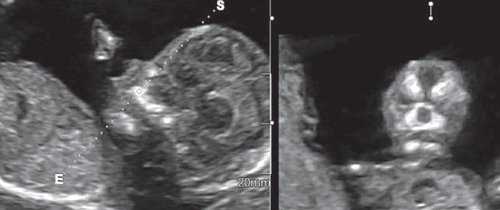

При эхографии в срок 13 недель 3 дня фетометрические параметры плода соответствовали гестационной норме, толщина воротникового пространства составила 1,5 мм; длина костей носа - по 2,5 мм. При трансвагинальном сканировании были обнаружены: затылочное энцефалоцеле размерами 7,4х3,5х3,7 мм (рис. 1), полидактилия кистей (рис. 2), увеличенные кистозно-измененные почки: правая - 28,5х21,3 мм; левая - 26,4х18,7 мм (рис. 3). Объем амниотической полости был нормальным для данного срока.

(Слева) ТАУЗИ плода в I триместре. Определяется умеренное утолщение воротникового пространства (кали-перы). По поводу неровных контуров задней части свода черепа выполнено ТВУЗИ.

(Справа) ТВУЗИ подтверждает наличие дефекта задней части свода черепа, а также затылочного энцефалоцеле крупных размеров, содержащее мозжечок целиком. Показан тщательный поиск других пороков развития.

(Слева) Тот же плод. УЗИ брюшной полости, фронтальная плоскость. С обеих сторон определяются увеличенные кистозно-измененные почки. Необходимо помнить, что объем амниотической жидкости в I триместре может быть в норме, даже несмотря на тяжелое двустороннее поражение почек.

(Справа) Во время скринингового УЗИ плода в I триместре, выполненного во время последующей беременности у той же женщины, обнаружено энцефалоцеле. Синдром Меккеля-Грубера имеет аутосомно-рецессивный тип наследования, риск повторного возникновения составляет 25%.